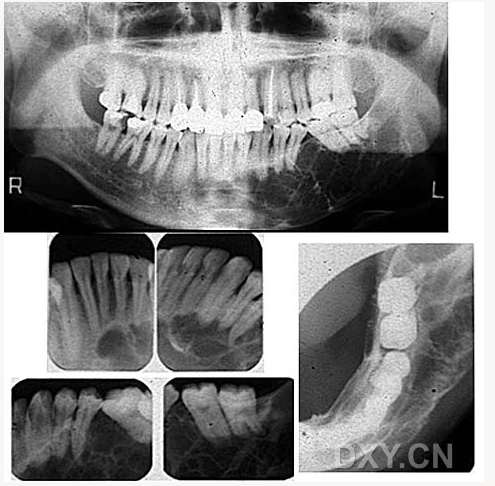

牙源性鈣化囊腫

牙瘤!

牙源性鈣化囊腫    牙瘤!

牙瘤

鼻腭囊腫

牙源性角化囊腫